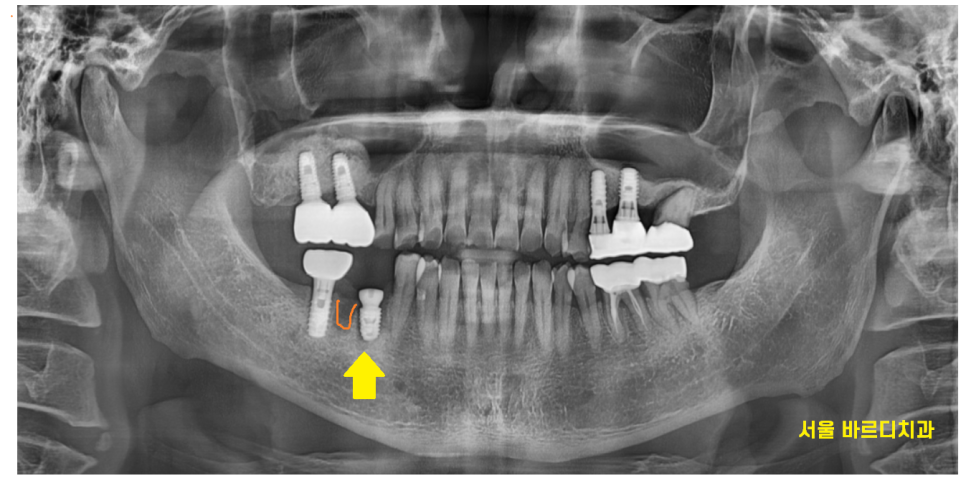

x-ray를 보실까요~?

24.03.29

오른쪽 아래 치아 뿌리 끝에 염증이 있습니다.

원인 해결이 안되니

반복적으로 잇몸 풍선마냥

부풀었다 가라앉았나보네요